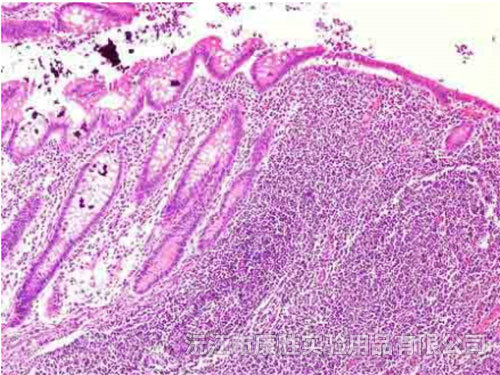

教学用病理切片

急性蜂窝织性阑尾炎

大叶性肺炎

风湿性心肌炎切片

小叶性肺炎切片